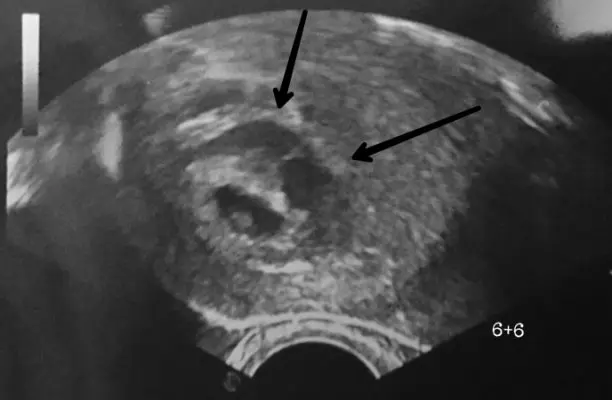

Wie sieht ein subchorionisches Hämatom im Ultraschall aus?

Subchorionische Hämatome können im Ultraschall erkannt werden. Sie erscheinen als dunkle, flüssigkeitsgefüllte Bereiche zwischen der Fruchthülle und der Gebärmutterwand. Die Größe und Form des Hämatoms kann variieren.